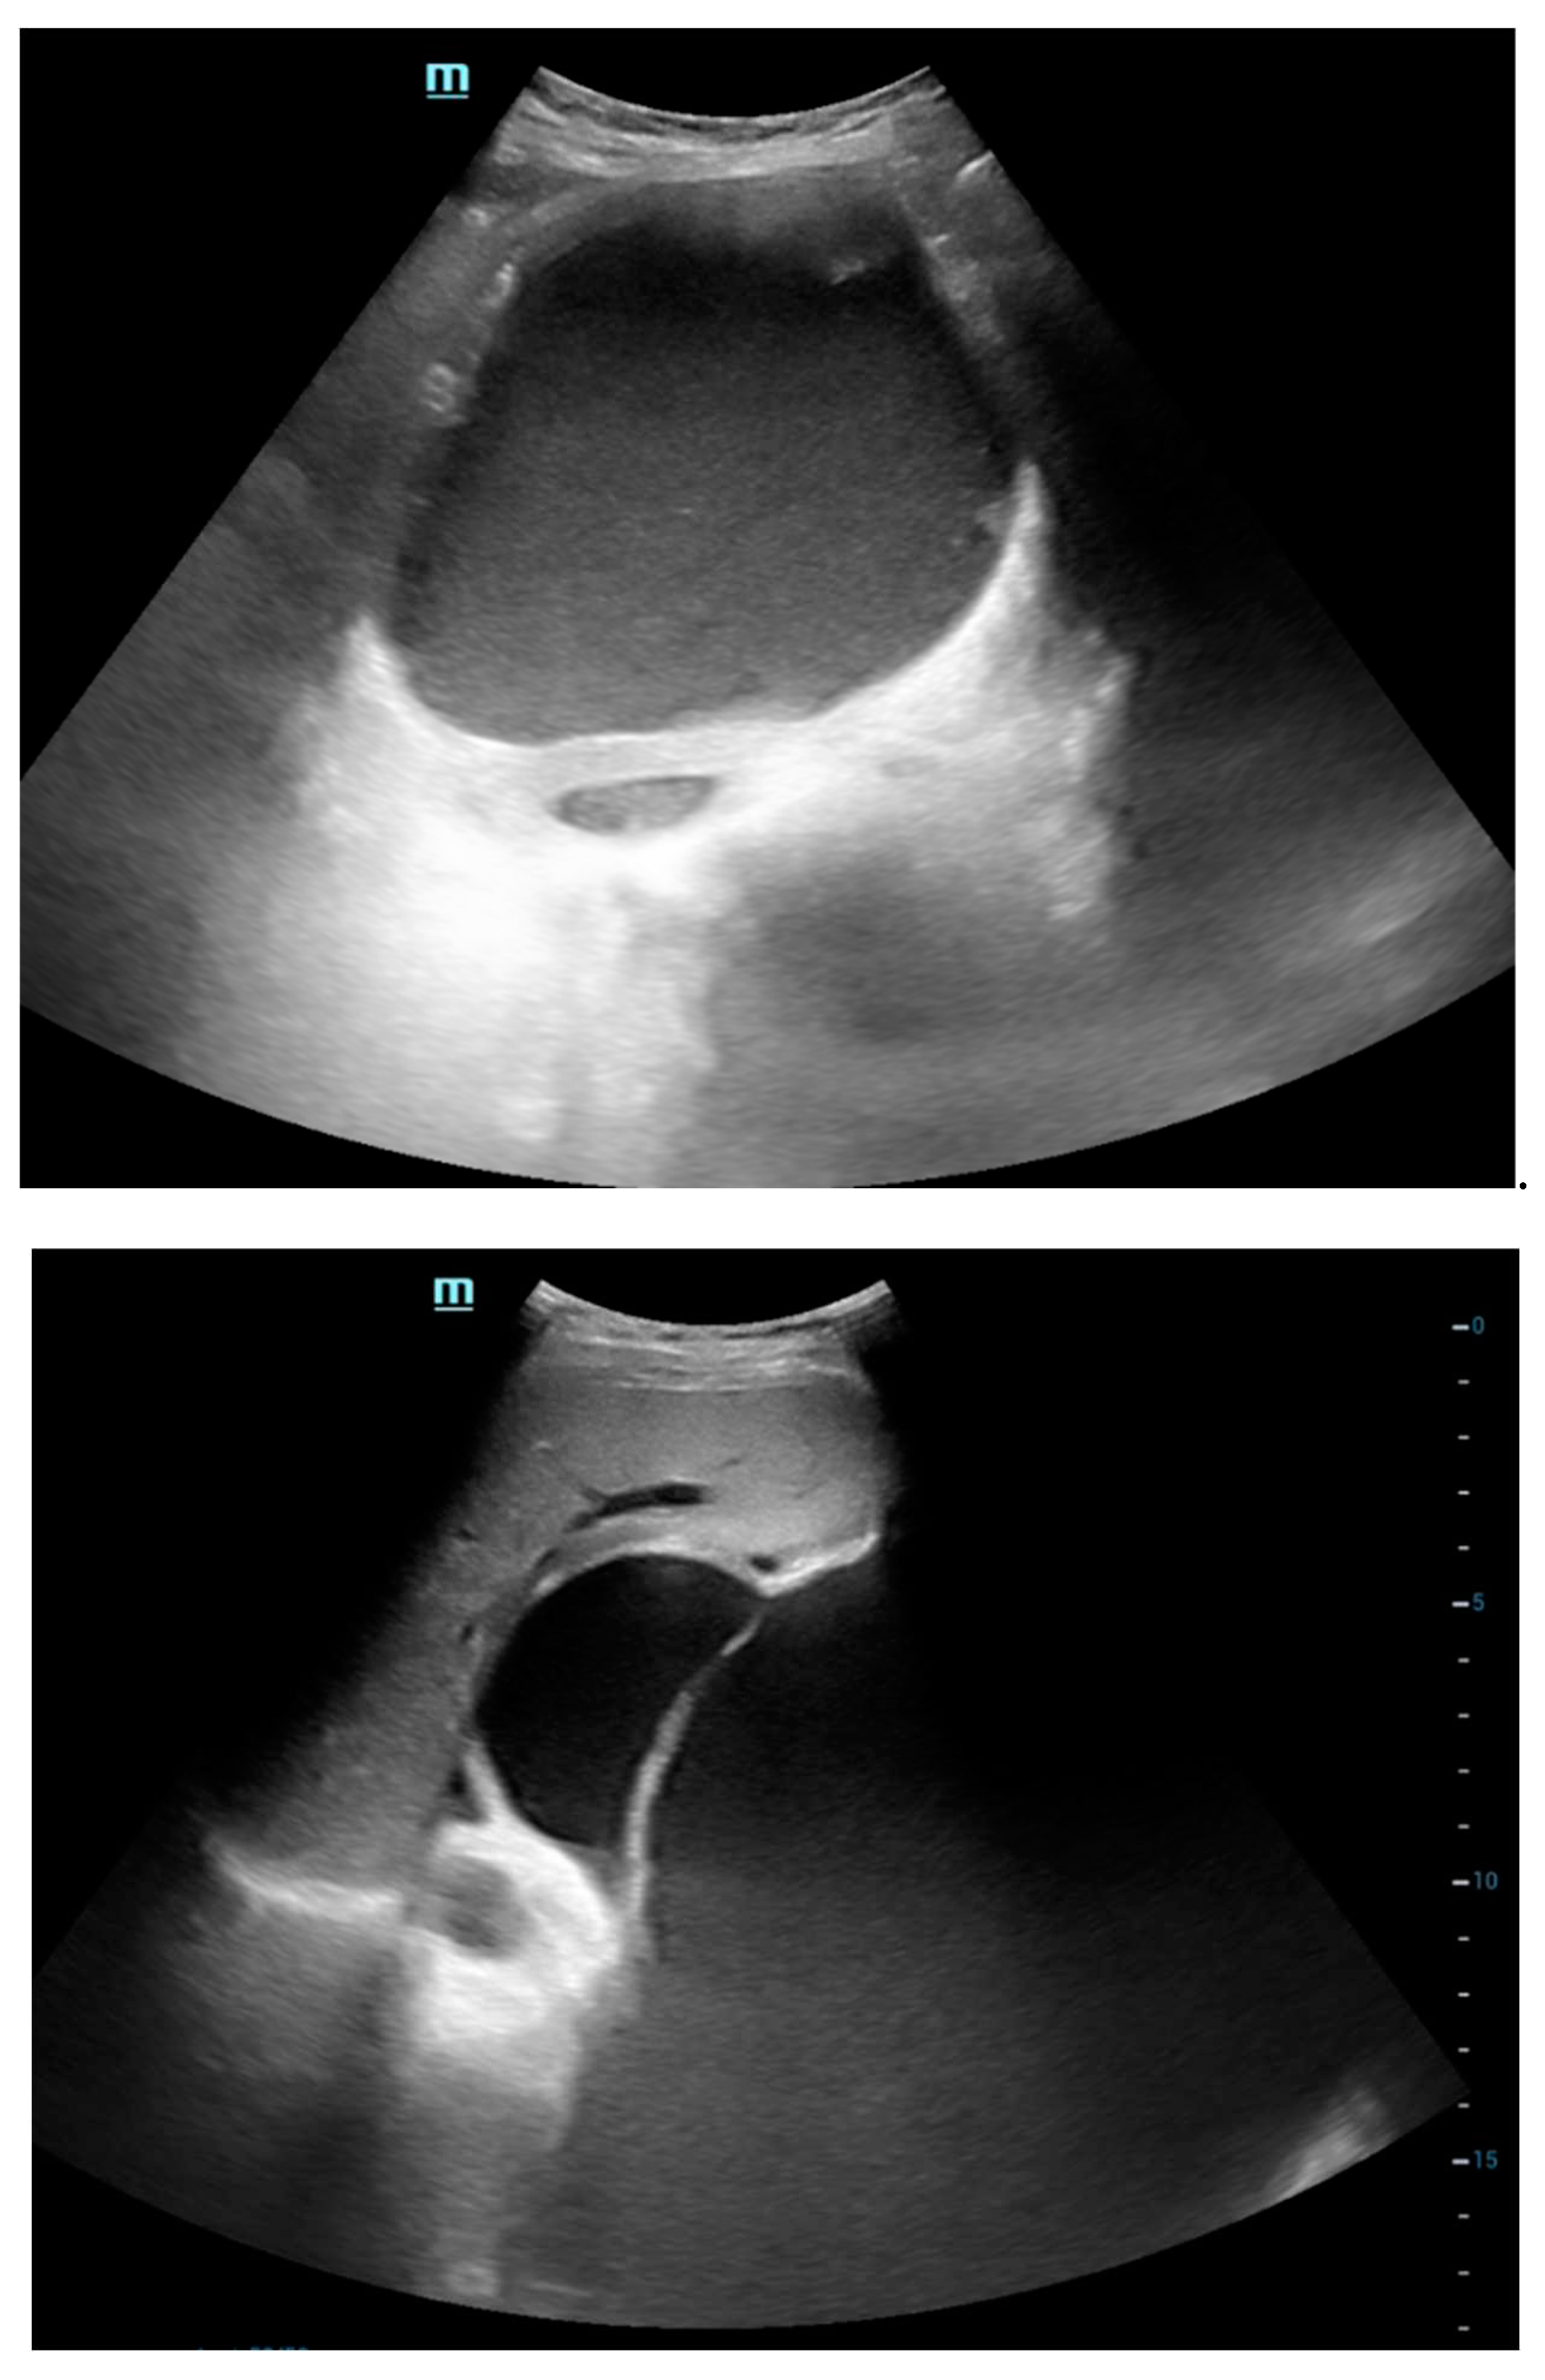

Ultrasound Abdomen

The ultrasonography (USG) findings reveal a sizable lobulated cystic lesion characterized by internal septations and dense echoes, extending throughout the abdomen and pelvis, with its upper boundary reaching the epigastric region. Notably, one of the septa in the left hypochondriac region exhibits a maximum thickness of approximately 7 mm. No solid components were discerned within the lesion. In the epigastric region, the lesion exerts pressure on and displaces the stomach in a superior direction. Additionally, the lesion causes peripheral displacement of bowel loops. These findings provide a comprehensive description of the observed abnormalities, offering valuable insights into the nature and extent of the cystic lesion.

Preprints 94567 g002